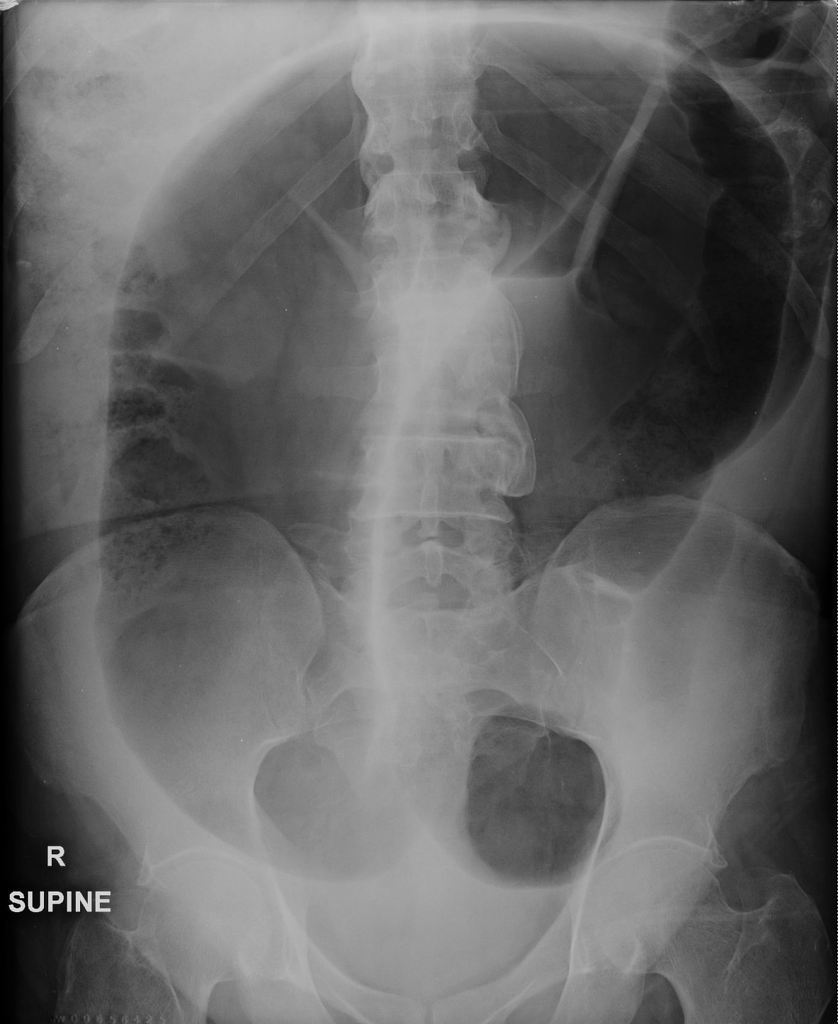

How to approach a AXR?

Image quality

BBC approach:

Bowel + other organs

Bones

Calcification

Presenting

How can you distinguish the small bowel?

Mucosal folds = valvulae conniventes - seen across full width of bowel

How can you distinguish the large bowel?

Pouches that protrude into lumen = haustra

What are the spaces in between the haustra called?

Plicae semilunaris

What is the 3/6/9 rule?

Diameter of intestines should be no greater than:

3cm in small bowel

6cm for colon

9cm for caecum